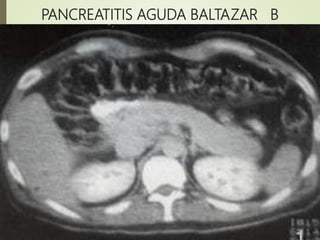

PANCREATITIS AGUDA BALTAZAR B

o Criterios radiológico de gravedad de Balthazar

El sistema desarrollado por

Balthazar valora La extensión de

la necrosis pancreática y

presencia de lesiones

extrapancreáticas en niveles de

puntuación de 0-10, en que la

puntuación 7-10 se asocia com

mayor mortalidad 17% y

morbilidad 92%